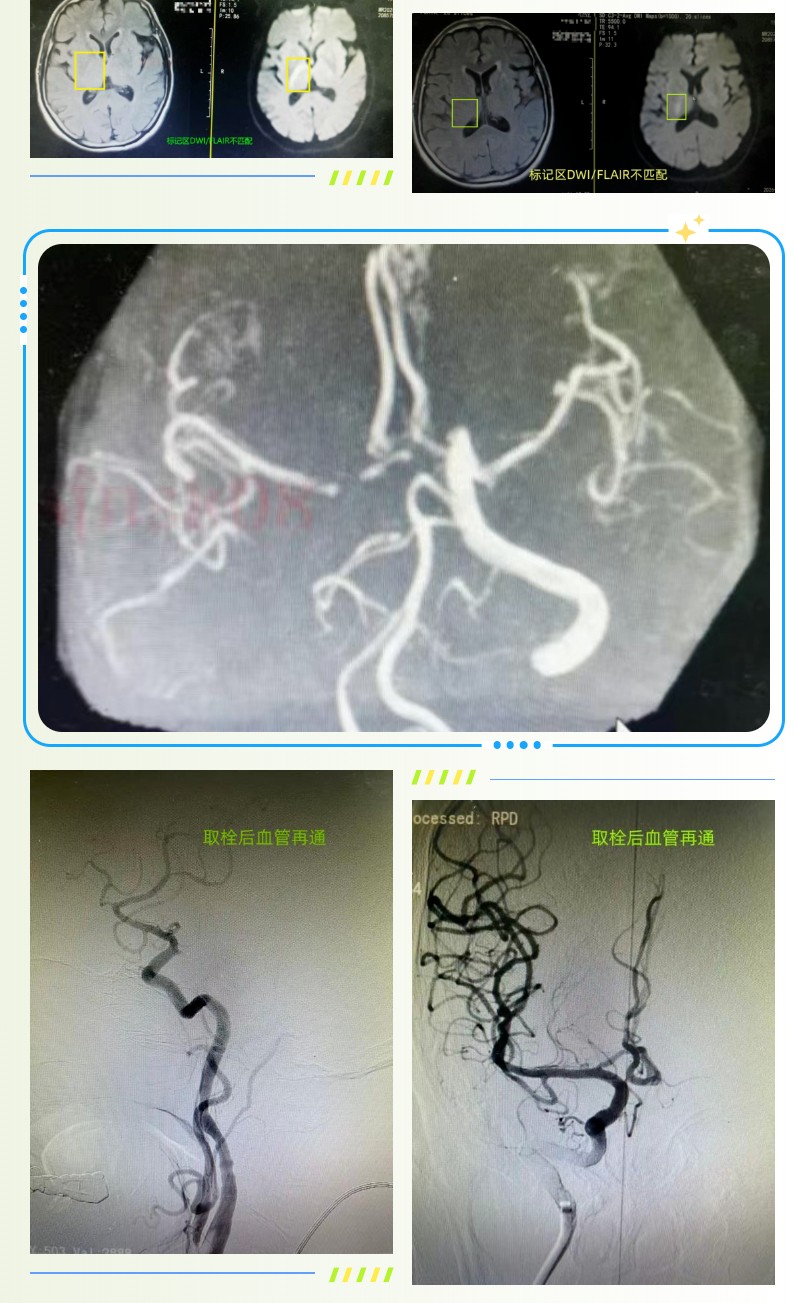

75岁的宋大娘因心慌、纳差、精神差入住泰安市第一人民医院心内科,老人既往有冠心病、充血性心力衰竭及心房颤动病史,长期口服利伐沙班进行抗凝治疗。入院当晚凌晨0时,宋大娘肢体活动一切正常,如厕后正常入睡,谁料次日晨7时醒来后,突发言语不清、左侧肢体活动障碍的症状。神经内三科医师接到会诊请求后第一时间赶往病房,结合症状快速判断为急性缺血性脑卒中(醒后卒中),为患者进行NIHSS评分达12分,情况十分危急。神经内科介入团队迅速响应,神经介入科主任王伟、神经内三科副主任张松第一时间确定诊疗方案,当即启动脑卒中绿色通道,快速联系核磁共振室,为患者紧急行颅脑MRI+MRA 检查。检查结果提示患者 DWI/FLAIR 不匹配,存在缺血半暗带,颅脑MRA 显示右侧颈内动脉闭塞,这意味着患者脑部仍有可挽救的脑组织,为后续精准救治提供了关键依据。

结合宋大娘的心房颤动病史及影像学检查表现,团队判断其 TOAST 分型为心源性栓塞型,患者末次正常时间为凌晨0时,影像学指征明确,具备急诊溶栓及介入治疗的条件。但考虑到患者长期口服利伐沙班,治疗方案的选择需更加谨慎,王伟主任与患者家属进行充分、细致的沟通,全面讲解了机械取栓术、桥接治疗及保守治疗三种方案的获益与潜在风险,家属商议后决定采取机械取栓术。就在术前查体时,患者左侧肢体活动较前出现一定恢复,家属见状产生了犹豫,王伟凭借丰富的临床经验判断,这一情况大概率是栓子部分逃逸所致,患者仍存在再栓塞及病情突然加重的风险,随即建议为患者行急诊脑血管造影+必要时机械取栓术,家属表示理解并同意。术中造影结果证实了医师的判断,患者右侧颈内动脉依旧处于闭塞状态,且存在大量栓子负荷。为了让家属更全面地了解手术情况,张松再次与家属沟通,详细说明手术路径、具体操作方式、费用构成以及相关医保报销政策,在家属充分知情并同意后,介入团队立即为患者开展机械取栓术。整个手术过程高效顺利,历时不足1小时便成功完成,术后宋大娘的四肢活动即刻恢复正常,言语也变得流利,术后次日复查颅脑CT显示,患者核心梗死区体积较前明显缩小,救治效果十分显著。